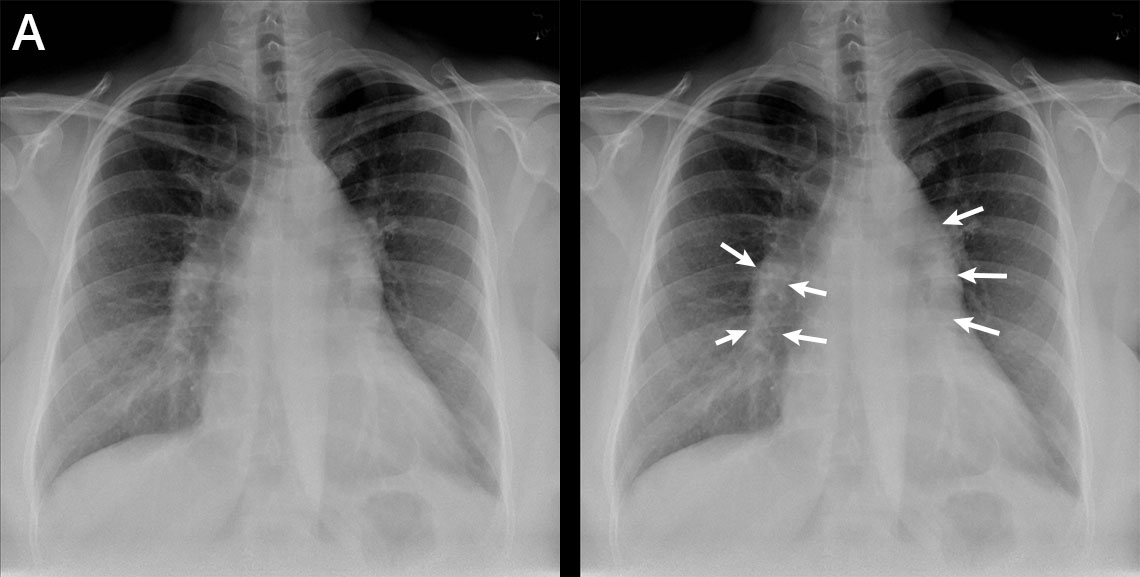

Kohonnut keuhkoverenpaine (kuva ilman löydösmerkintöjä).

Nuorella naisella oli hengenahdistusta ja huonovointisuutta.

Kohonnut keuhkoverenpaine (kuva löydösmerkinnöin).

Keuhkokuvassa näkyvät kohonneeseen keuhkoverenpaineeseen sopivat löydökset. Lisäksi keuhkovaltimot ovat prominentit (nuolten väliin jäävä alue).